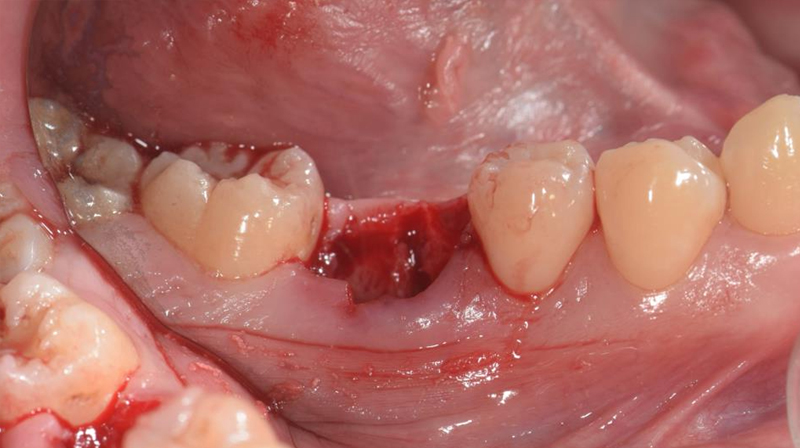

拔除右下第一大臼齒

拔除智齒,固定至第一大臼齒缺牙區域

智齒固定